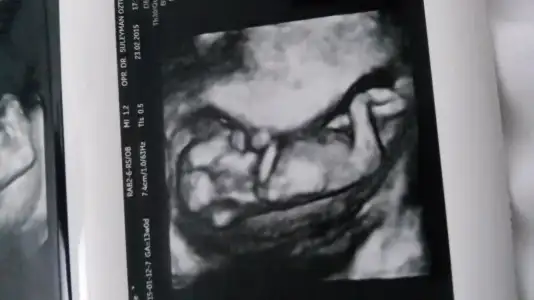

dr soylemeden siz gorun genital nub teorisi ( bebegin cinsiyeti)

Burda nub teorisine göre kimi erkek kimi kız dedi....Hislerim bazen erkek bazen kız....Rüyamda bir kız bir erkek görüyorum...Doktorum da bir şey demiyor...Ya tamam gerçekten sağlıklı olsun önemli olan bu da insan merak ediyor ama ya :(